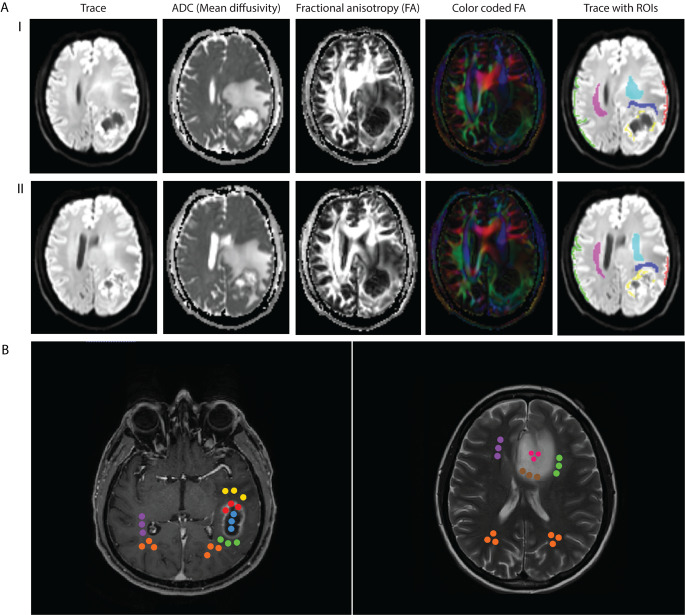

Postprocessed MD and FA maps were exported from the SIEMENS console and analyzed with MRIcron (Version: 2MAY2016; https://www.nitrc.org/projects/mricron). ROIs were defined as tumor tissue of the marginal zone of the lesion (TU), white matter adjacent to the lesion (AWM), as well as distant ipsilateral and contralateral grey and white matter as shown in Fig. 1 A. The marginal tumor zone was chosen over the whole tumor in order to sample live tissue and avoid cystic or necrotic areas. ROIs were manually drawn over multiple slices in which tumor structures could be clearly identified. ROIs were similar for all glioma entities. Mean values of FA and MD were exported for each ROI. Additionally, perifocal edema volume in the vicinity of the tumor mass was determined by using a non-threshold-based manual segmentation tool (Horos, Horosproject.org).

Fig. 1.

(A) Representative images of a DTI scan are presented for two different axial slices from the same patient (I & II). The regions of interest (ROI) for the analysis of our first cohort A are color labeled and consist of the marginal tumor zone (yellow), white matter adjacent to the tumor (dark blue), ipsilateral (red) and contralateral (green) cortex as well as ipsilateral (cyan) and contralateral (magenta) white matter. (B) Representative slices of a T1-MPRAGE image of a patient with GBM, IDH-wildtype (left), and a T2-weighted image of a patient with astrocytoma, IDH-mutant, CNS WHO Grade 2 (right) are shown. Colored circles illustrate the definition of regions of interest (ROI) for our second cohort B. In GBM patients and IDH-mutant astrocytoma CNS WHO Grade 4, three spheric ROIs were defined in each contrast enhancement (red), necrosis (blue), peritumoral white matter (green), edema (yellow), the area contralateral to the tumor in the opposite hemisphere (violet) as well as ipsi- and contralateral controls frontal or occipital depending on tumor position (orange, left image). In all other tumor entities (right image), three spheric ROIs were defined in each non-enhancing tumor (pink), marginal non-enhancing tumor zone (brown), peritumoral white matter (green), edema (not present), the area contralateral to the tumor in the opposite hemisphere (violet) as well as ipsi- and contralateral controls frontal or occipital depending on tumor position (orange) and contrast enhancement/ necrosis if present

ROIs were defined based on MPR-/ T2- and FLAIR sequences depending on the visibility of the particular tumor entity in the specific sequences. To avoid possible effects due to different ROI volumes, three-dimensional spheres with a fixed diameter of 4 mm were defined in subcortical white matter. In this cohort, two sets of ROIs were used depending on glioma entity. In GBMs and IDH-mutant astrocytoma CNS WHO Grade 4, we defined three spheres in each contrast enhancement, as well as spheres in areas of necrosis, peritumoral white matter (AWM), edema, the area contralateral to the tumor in the opposite hemisphere as well as ipsi- and contralateral controls frontal or occipital depending on tumor position. In the other tumor entities, ROIs were defined in non-enhancing tumor (NENH), marginal non-enhancing tumor zone (MARG-NENH), contrast enhancement if present, necrosis if present as well as the above-mentioned control regions. The TU ROI from cohort A is therefore represented by both the contrast enhancement ROI and MARG-NENH ROI in cohort B. Figure 1B illustrates the definition of ROIs. Minimum, mean and maximum FA and MD were exported for each ROI.